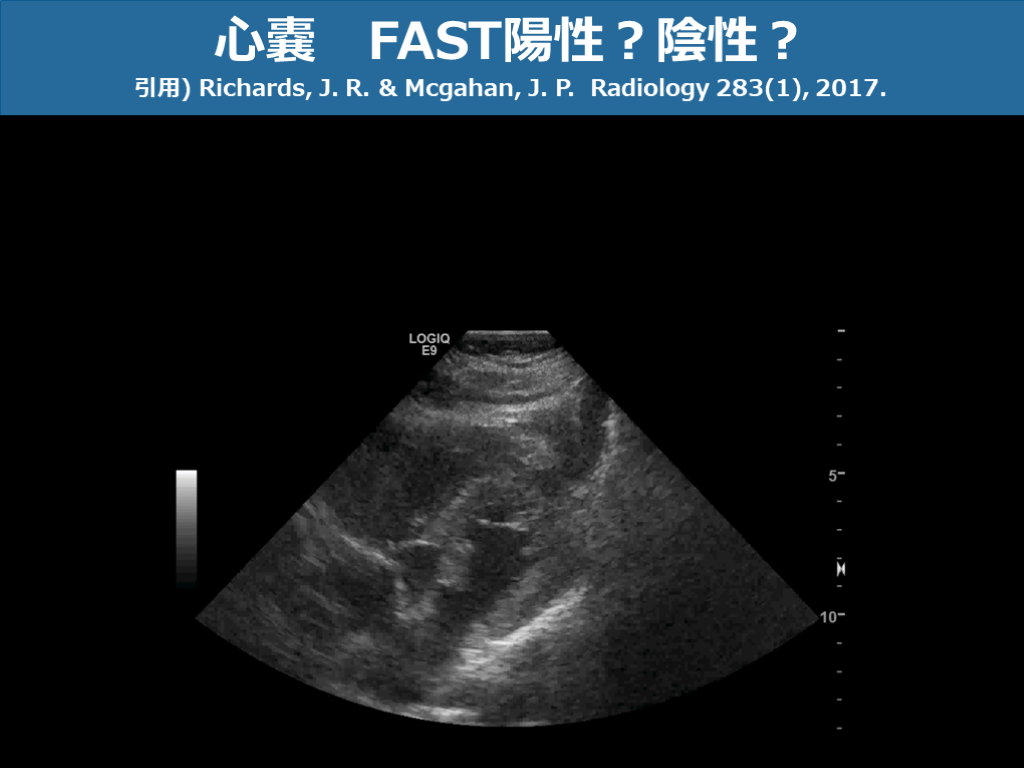

心嚢 FAST陽性?陰性? 引用) Richards, J. R. & Mcgahan, J. P. Radiology 283(1), 2017. スライド画像)広島大学病院 演者作成

心嚢 FAST陽性?陰性? 引用) Richards, J. R. & Mcgahan, J. P. Radiology 283(1), 2017. スライド画像)広島大学病院 演者作成 心尖部周囲に少量の心のう水貯留あり